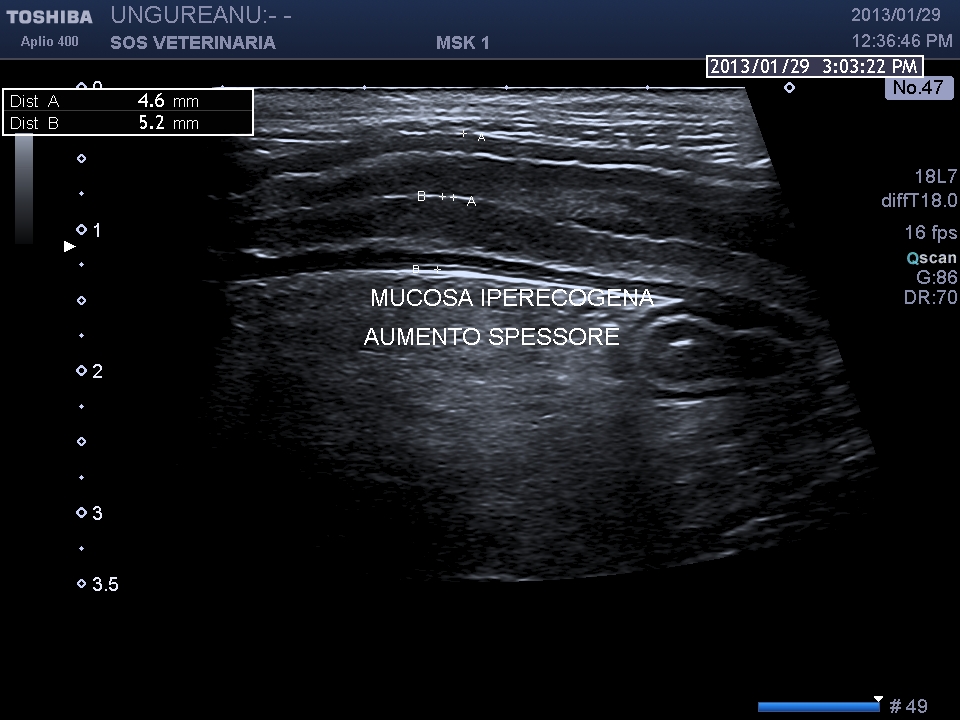

gatto comune europeo 9 aa ABC_8738

Le vie biliari del gatto hanno caratteristiche diverse rispetto al cane il dotto pancreatico principale raggiunge il coledoco  prima che questo defluisca nella papilla duodenale maggiore (nel cane lo sbocco e’ indipendente) ,inoltre il dotto accessorio  sfocia nella papilla minore ,un processo ostruttivo distale porta quindi a distensione  di entrambe le componenti  ,l’iperplasia della parete delle vie biliari  puo’ essere indicativa di flogosi o di cronicita’ dell’ostruzione  (in questo caso la parete e’ normale) ma come sopraesposto la diagnosi richiede spesso invasivita’ ,questo caso purtroppo  non ha seguito nessuna diagnosi ,il soggetto non ha risposto alla terapia cortisonica (l’unica che ha voluto tentare il proprietario) e antibiotica e si e’ perso nel foll’up, Una laparotomia esplorativa con campionamento del tessuto iperplastico  e coltura biliare era a mio avviso unica opzione possibile per una corretta diagnosi .

Il caso si mostra interessante sul piano dell’imaging che evidenzia la complessita’ delle vie biliari extraepatiche e pancreatiche dilatate.